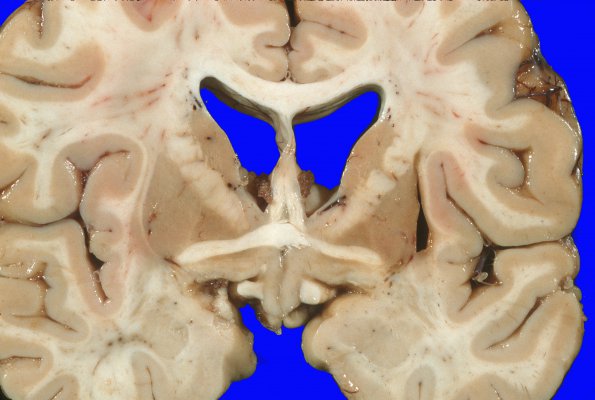

Higher magnification showing bilateral discoloration and slight atrophy of the globus pallidus.